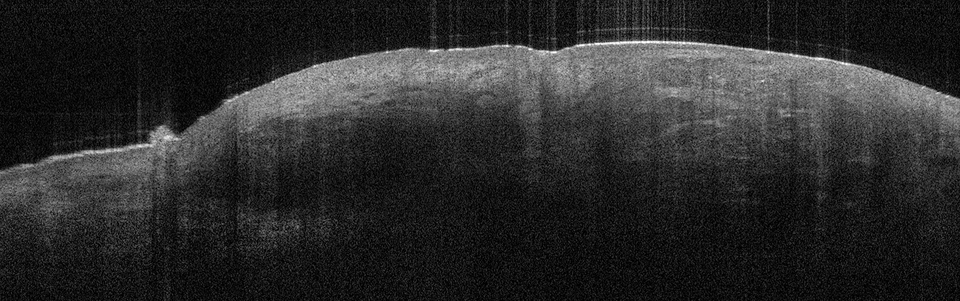

Die Tumorzellverbände des BCC erkennt man in der Aufnahme als signalarme, ovoide Nester mit dunk­lem Randsaum, die von hellem Stroma umgeben sind. Die Epidermis ist abgeflacht, Teleangiektasien kann man als kleine dunkle Löcher sehen. Eine aktinische Keratose sieht anders aus: In diesem Fall sind Hornschicht und Epidermis verdickt, oft sieht man auch weiße Streifen in der Hornschicht, so die Referentin. In Abgrenzung zum Plattenepithelkarzinom erscheint die dermoepidermale Junktion bei der aktinitischen Keratose intakt. Beim Plattenepithelkarzinom werden zudem helle Bereiche deutlich, bei denen es sich um Hornzysten handelt.

Beim nodulären BCC zeigen sich die typischen ovoiden knotigen Tumorzellverbände. Die über dem BCC liegende Epidermis ist verdünnt. Beim nodulären BCC zeigen sich die typischen ovoiden knotigen Tumorzellverbände. Die über dem BCC liegende Epidermis ist verdünnt. © Prof. Dr. Julia Welzel